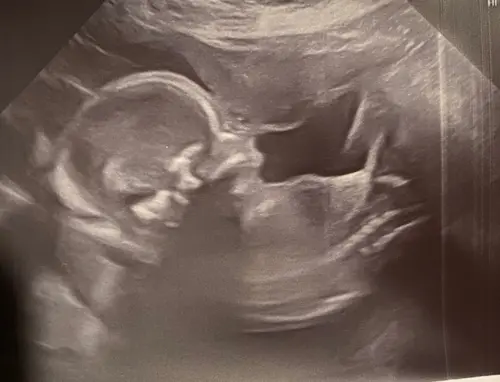

Interessant om dit te zien, ik las over de skull theorie en jouw echo’s lijken dan wel echt op een jongetje skull. Mijn echo van mijn kindje ziet er ook echt zo uit.. heel benieuwd of het ook een jongetje is. Mijn eerste is een dochter en haar echo had destijds een veel ronder gladder hoofje zeg maar

Dit is een echo van mijn dochter, ergens rond de 20 weken. Deel gerust jouw echo’s, ben benieuwd of ze gelijken op die van mijn zoon!

Volgens mij heeft de skull theory weinig wetenschappelijke basis en toch vind ik dat de schedels van meisjes zichtbaar zachter en ronder zijn. Maar de ene keer vind ik het wel duidelijker dan de andere keer.